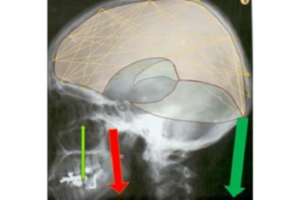

- Estudio de movimientos intrínsecos del cráneo: Diferenciar entre movimientos causados por estructuras inferiores y deformaciones propias del cráneo.

El curso se desviará de algunas ideas osteopáticas tradicionales, centrándose en los principios RPG y respetando los descubrimientos actuales en ciencias médicas. Además, se abordarán las estructuras intracraneales y su influencia en la postura, destacando la importancia de la duramadre y las membranas de tensión recíproca en el equilibrio de tensiones y la salud del sistema nervioso central.